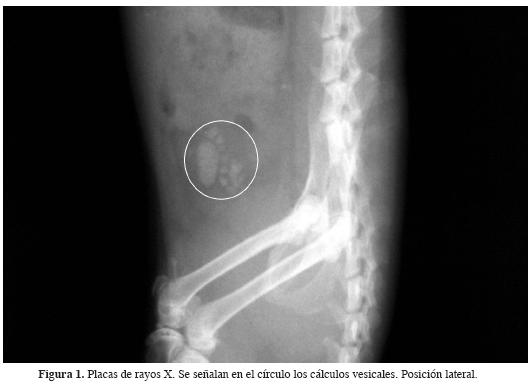

Inducción de cálculos vesicales. Se indujo la formación de cálculos mediante cirugía. Dos horas antes de ésta, se mantuvo a los animales sin alimento y con libre acceso al agua. Se desinfectó el área abdominal inferior con jabón quirúrgico. Se realizó una incisión hasta ubicar la vejiga urinaria, en ella se colocó una placa de magnesio de 0.006 g previamente desinfectada. Se suturó la herida y se aplicó desinfectante y cicatrizante Aluspray® Vétoquinol, S.A. Se estableció un periodo de 28 días para la recuperación de las ratas y la formación de los cálculos (Vargas y Pérez, 2002). Posteriormente se tomaron placas de rayos X en proyecciones ventrodorsal (VD) y en sentido lateral izquierdo a lateral derecho (Li-Ld), para corroborar la presencia de los cálculos en los organismos utilizados en los ensayos biológicos.

Al desarrollo de la litiasis vesical, se le dio seguimiento mediante la toma de placas de rayos X. Esta valoración se realizó previa a la aplicación de los tratamientos farmacológicos (Figura 1). El resultado del análisis de difracción de rayos X de los cristales formados fue la identificación de cristales de estruvita: fosfato amónico magnésico exahidratado (NH4MgPO4·6H20).